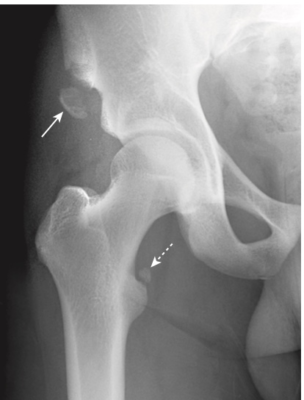

- Ví dụ: Trượt chỏm xương đùi (Slipped capital femoral epiphysis, SCFE):

- thường xảy ra ở trẻ trai cao và nặng, trong giai đoạn phát triển nhanh, do chấn thương, loạn dưỡng xương, và các bệnh nội tiết như là nhược giáp.

- Chỏm xương đùi trượt xuống dưới, vào trong và ra sau so với cổ của xương đùi (Hình 6).

- 25% trường hợp xảy ra hai bên, và có thể dẫn đến hoại tử vô mạch của chỏm xương đùi bị trượt vì sự cung cấp máu bị gián đoạn trong khoảng 15% trường hợp.